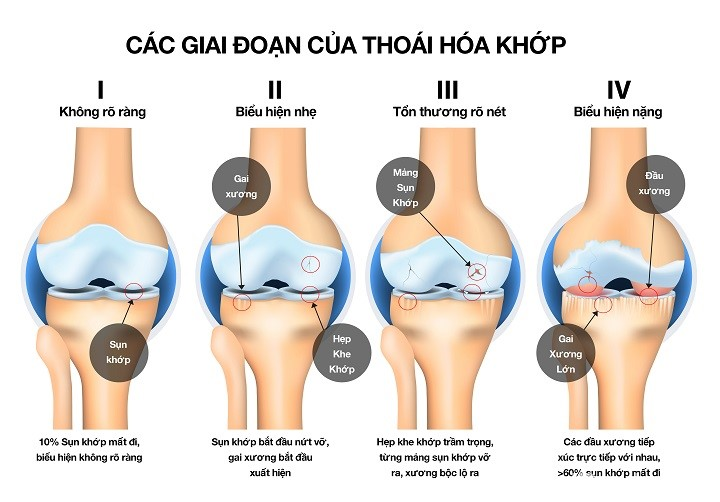

Thêm nữa khi về già, sụn khớp sẽ dần mất nước làm suy giảm khả năng cản lực ma-xát tác động lên xương. Dây chằng & các mô liên kết khác của sụn cũng trở nên kém đàn hồi, khiến biên độ hoạt động của khớp giảm, khi có tác động mạnh có thể gây viêm và đau khớp. [2]

Các giai đoạn của thoái hóa sụn khớp